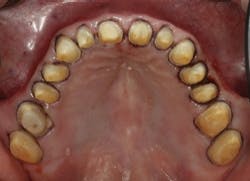

Fig. 1 — Maxillary arch using the two-cord technique with Ultrapak (Ultradent) cord soaked in aluminum chloride, sizes 00 and 0.

Fig. 2 — Corresponding impression with Identium (Kettenbach). Making an impression of multiple preparations is one of the most difficult procedures in all of dentistry, and can be very stressful for the patient and dental team.